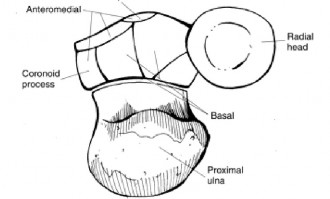

The correct answer is (C). This structure is a thickening of the coracohumeral ligament that starts anteriorly just posterior to the short head of the biceps tendon on the coracoid process, extends posteriorly through the edge of the avascular zone of the supraspinatus and infraspinatus, and ends at the inferior edge of the infraspinatus. One proposed function of the cable is to act like a cable in a suspension bridge, helping to evenly distribute forces on the humeral head produced by the rotator cuff (see Fig. 2–6).

Figure 2–6_Illustration showing the rotator cable and rotator crescent. B, rotator crescent; C, rotator cable; BT, biceps tendon; I, infraspinatus; S, supraspinatus; TM, teres minor. (Redrawn from Burkhart SS, Lo IKY. Arthroscopic rotator cuff repair. _J Am Acad Orthop Surg. 2006;14(6):333–346.)

The rotator crescent (Answer A) is the thin tissue that exists lateral to the rotator cable medial to the attachment of the supraspinatus and infraspinatus. It is composed on the tendons of these two rotator cuff muscles (see Fig. 2–6).